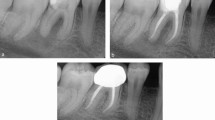

Non-surgical RCT should be carried out using 0.5-5.25% sodium hypochlorite.64 A penultimate rinse with ethylenediaminetetraacetic acid may also be used.68 Two-visit endodontic treatment, with an interim dressing of calcium hydroxide, may improve periodontal outcomes65,66 compared to single-visit treatment, with a tentative suggestion that subgingival PMPR should be done while the intra-canal dressing is in situ. The biological basis for this lies in the fact that the initiation of non-surgical RCT and intra-canal dressing reduces the bacterial load and levels of inflammatory mediators, such as lipopolysaccharide, reducing the potential for cross-seeding between necrotic pulp and inflamed periodontal tissues8,66,67 (Fig. 9).

Case of localised periodontitis in a young patient, including an EPL affecting tooth 43. Initial presentation of tooth 43 with deep periodontal probing depths >6 mm affecting buccal lingual and distal aspects of the tooth combined with diffuse apical pathology combined with marginal bone loss. a, b) The tooth was also over-erupted but not mobile. c, d) RCT was undertaken over two visits, with recontouring of the crown to improve appearance. Targeted subgingival PMPR was undertaken immediately after completion of the RCT. e, f) At six-month review, probing depths had reduced to 4 mm with resolution of the inflammation, no bleeding on probing and radiographic bone fill seen. The tooth was placed into a maintenance phase